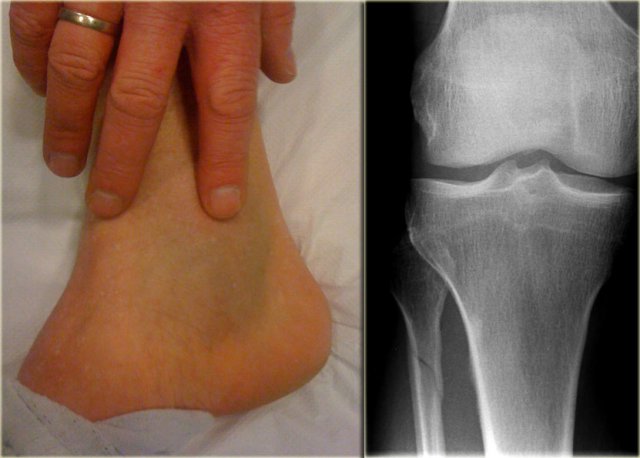

On the left images of a patient with a hematoma on the medial side.

• First impression

We can exclude a Weber A or B fracture, because we see no fracture.

A high Weber C is still a possibility, i.e.

• medial ligament rupture

• high fibular fracture

• posterior syndesmosis rupture.

• Re-examination

Additional radiographs of the lower leg were taken and demonstrated a high fibular fracture, also known as Maisonneuve fracture.

• Final report

Weber C stage 4, i.e. medial collateral ligamentous rupture, rupture of the anterior syndesmosis, high fibular fracture and probably a rupture of the posterior syndesmosis.

Teaching point No fracture on the radiographs of the ankle does not exclude an unstable ankle injury

This case demonstrates that there can be an unstable ankle injury that needs surgery even when the radiographs of the ankle do not show a fracture.